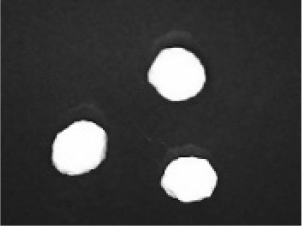

In addition to the disintegration endpoint studied using the USP disintegration apparatus, the pellets disintegrated into particles of various sizes when evaluated at a static position. A few drops of water were placed on the pellets on the opaque surface. A USB digital microscope (China) was connected to a computer to capture the disintegration process. Images were captured from the beginning until the pellet disintegrated or exploded into small fragments. Pellet images were acquired every 30 seconds. for formulations containing polyplasdone XL 10 and croscarmellose sodium.

Disintegration was evaluated at room temperature under static conditions. The camera captured images every 30 s ( Table 9), illustrating that MCC pellet X3 with mannitol and PEG 400 did not disintegrate. Within 120 s, cracks appeared in P5 pellets containing mannitol, PEG, and PPXL. As seen in the C4 pellets, they begin to explode into many fragments within 30 s. Moreover, the CP12 pellets containing PEG 400, mannitol, CCS, and PPXL began to explode into many loosely linked particles after 60 s, which quickly separated under the oscillating motion of the USP disintegration equipment. The photographs are compatible with the results mentioned above for the USP disintegration device. When the temperature was increased to 37°C, the disintegration caused the split into tiny fragments.

Table 9. Camera capture of pellet disintegration at different time intervals.

Pellet # 0 sec. 30 sec. 60 sec. 90 sec. 120 sec.

X3c9c3975f-9288-4951-a800-a8e9fc463382_GRA58.gif c9c3975f-9288-4951-a800-a8e9fc463382_GRA59.gif c9c3975f-9288-4951-a800-a8e9fc463382_GRA60.gif c9c3975f-9288-4951-a800-a8e9fc463382_GRA61.gif c9c3975f-9288-4951-a800-a8e9fc463382_GRA62.gif

P5c9c3975f-9288-4951-a800-a8e9fc463382_GRA63.gif c9c3975f-9288-4951-a800-a8e9fc463382_GRA64.gif c9c3975f-9288-4951-a800-a8e9fc463382_GRA65.gif c9c3975f-9288-4951-a800-a8e9fc463382_GRA66.gif c9c3975f-9288-4951-a800-a8e9fc463382_GRA67.gif

C4c9c3975f-9288-4951-a800-a8e9fc463382_GRA68.gif c9c3975f-9288-4951-a800-a8e9fc463382_GRA69.gif c9c3975f-9288-4951-a800-a8e9fc463382_GRA70.gif c9c3975f-9288-4951-a800-a8e9fc463382_GRA71.gif c9c3975f-9288-4951-a800-a8e9fc463382_GRA72.gif

CP12c9c3975f-9288-4951-a800-a8e9fc463382_GRA73.gif c9c3975f-9288-4951-a800-a8e9fc463382_GRA74.gif c9c3975f-9288-4951-a800-a8e9fc463382_GRA75.gif c9c3975f-9288-4951-a800-a8e9fc463382_GRA76.gif c9c3975f-9288-4951-a800-a8e9fc463382_GRA77.gif

The CP12 pellet disintegration process is depicted in the video in the supplementary material (refer to underlying data). The pellets swelled immediately before exploding and quickly disintegrating. The orphenadrine citrate pellets began to swell and cracks appeared after 120 s, which were easily separated under the oscillating motion of the USP disintegration equipment. The photographs are compatible with the results of the USP disintegration device. When the temperature was increased to 37°C, disintegration caused the fragments to split into smaller fragments. When the temperature was increased to 37°C, disintegration caused the split into tiny fragments. The pseudoephedrine hydrochloride pellets began to explode into several pieces of loosely linked particles within 120 s, which were easily separated by the oscillating motion of the USP disintegration equipment. The photographs were compatible with the results obtained from the USP disintegration device. When the temperature increased to 37°C, the disintegration caused the split into tiny fragments. Although this is not an official USP test, using video capture for disintegration validates Chamsai’s claim of quick disintegration.18